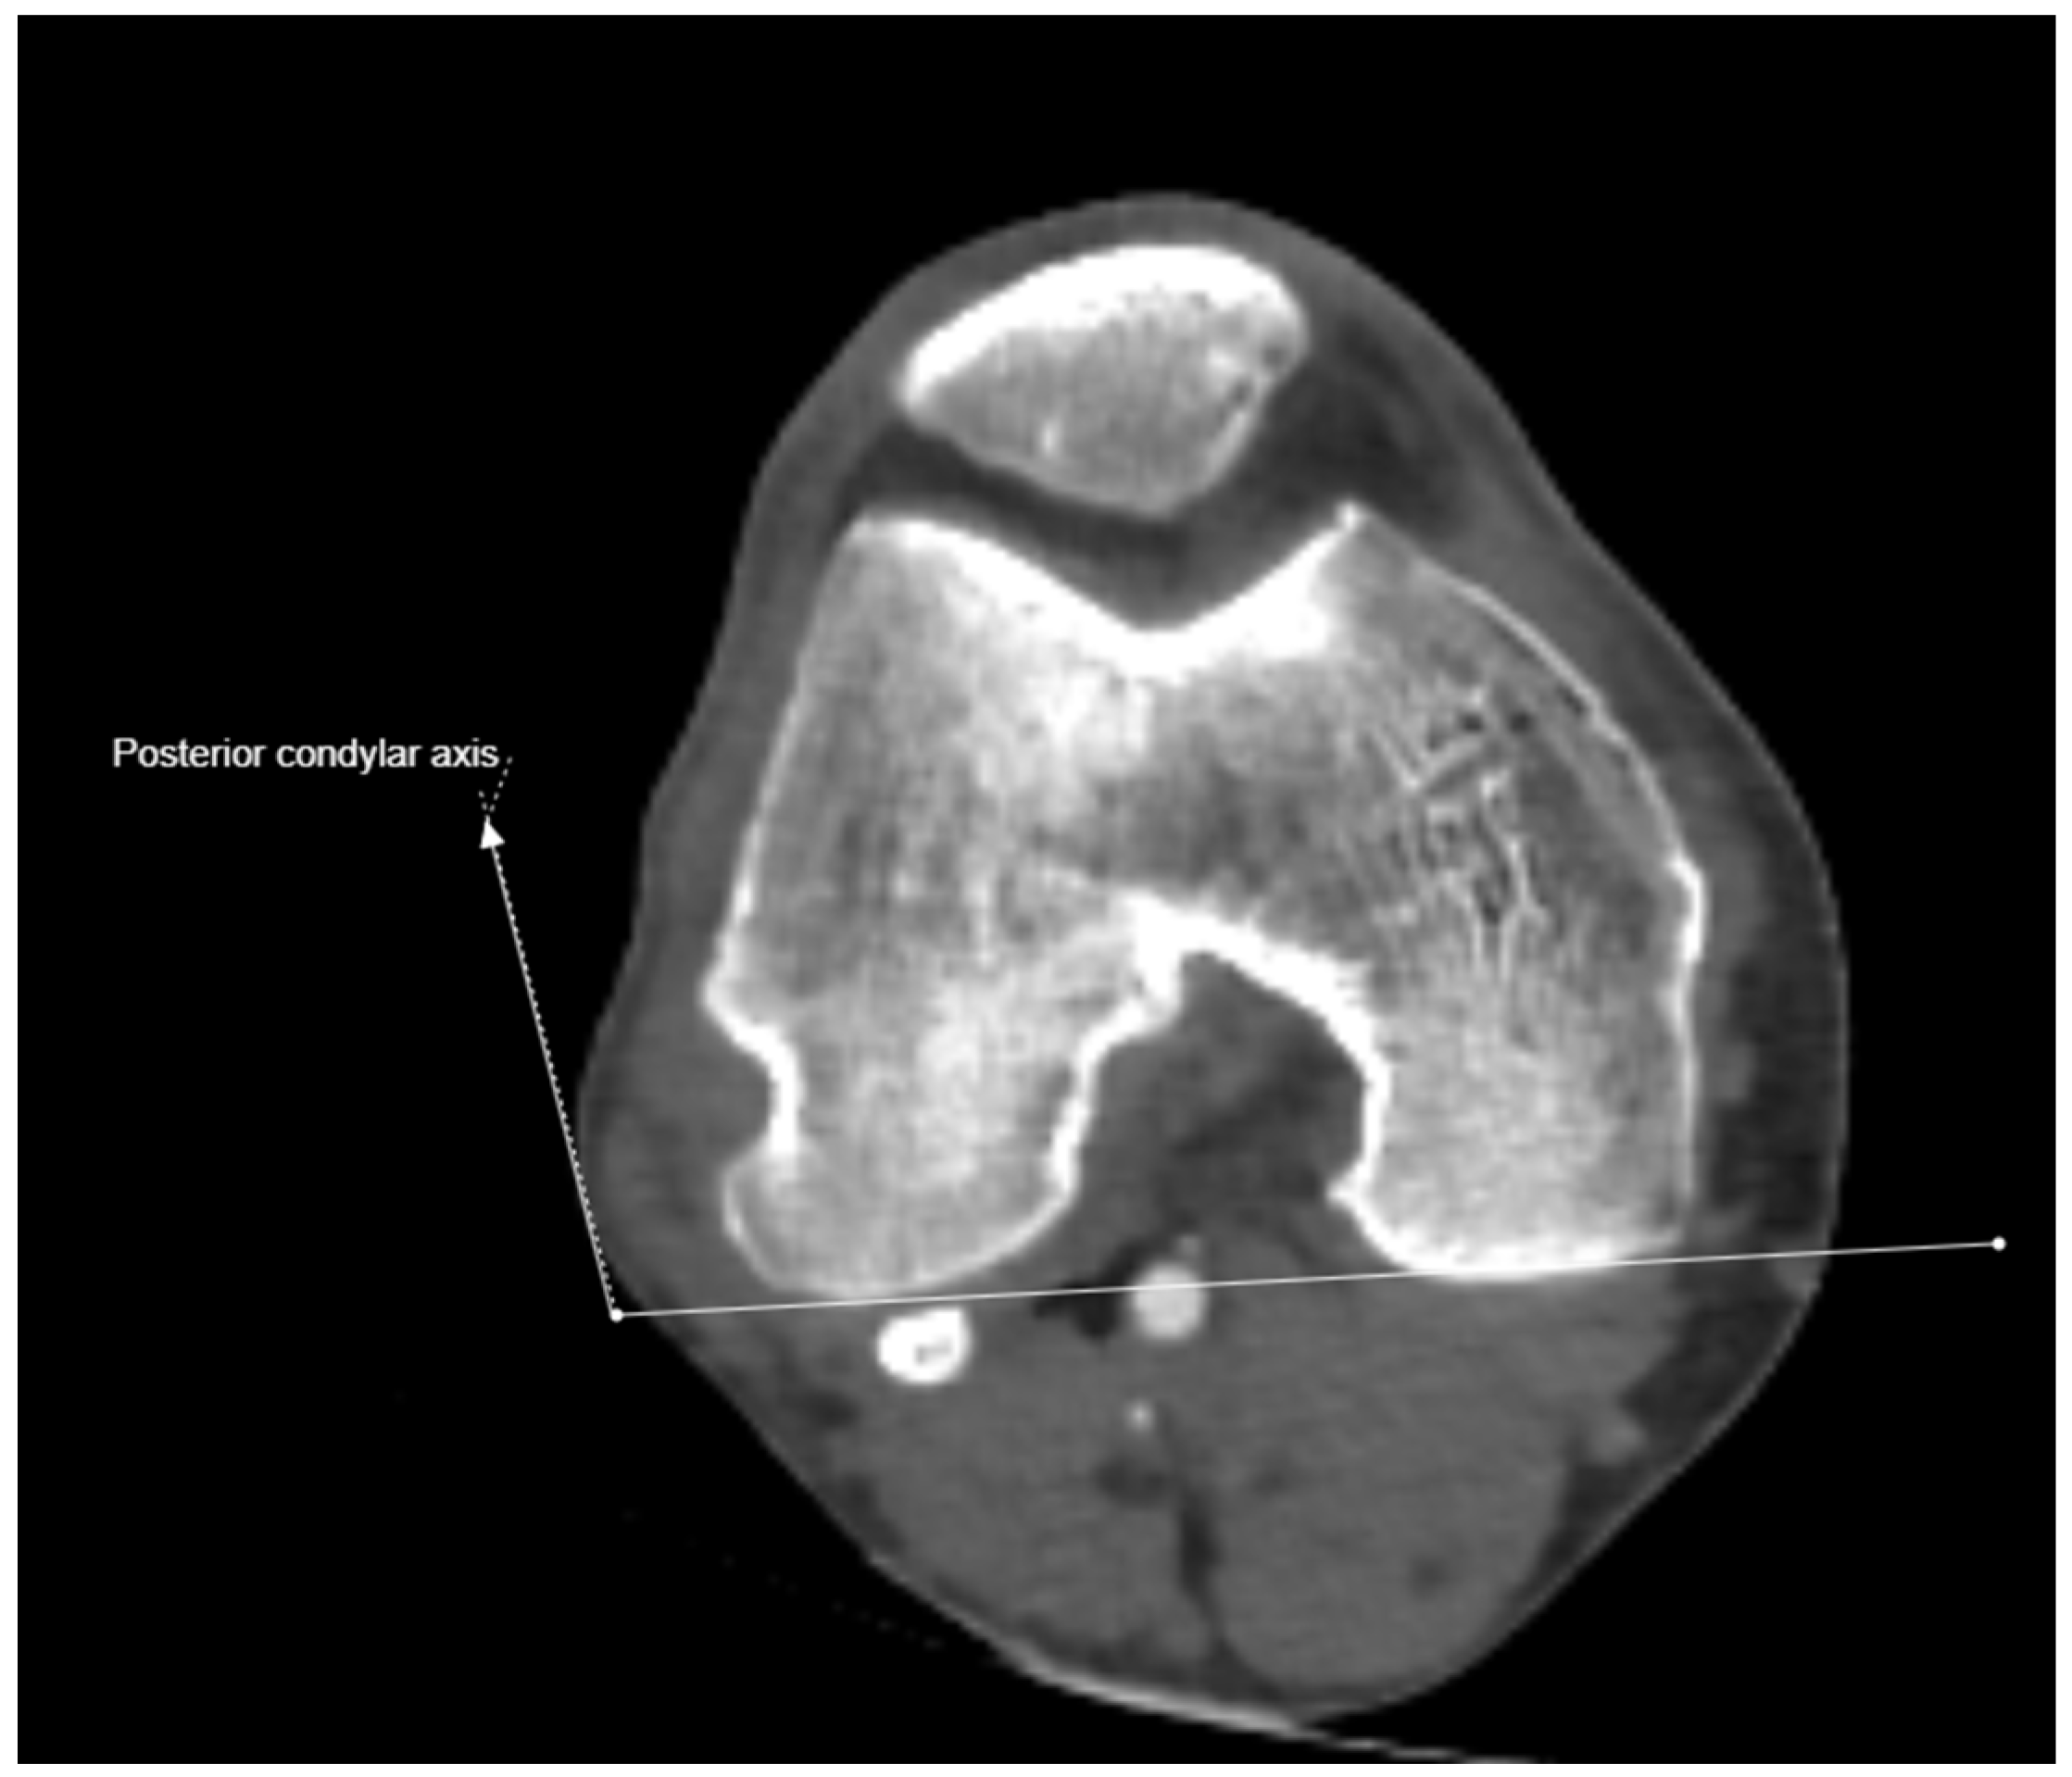

2.3. Imaging and Measurement Methods

| Posterior femoral cortex | 128.01 ± 29.59 (54.1–200.1) | 170.13 ± 29.96 (93.9–241.7) | 22.93 ± 6.04 (7.6–38.0) | −36.58 ± 11.30 (−79.2–−10.3) |